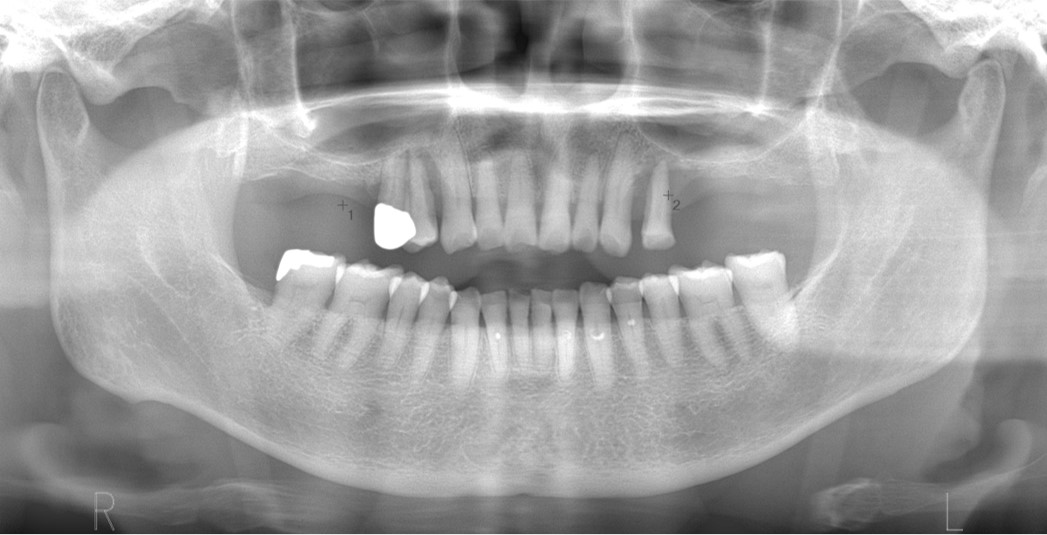

院長は、外科処置に関する口腔外科の専門医資格である公益社団法人日本口腔外科学会認定口腔外科専門医(第2055号)、NPO法人日本口腔科学会認定医(3-16046)、インプラントの専門医資格である公益社団法人日本口腔インプラント学会専門医(第1103号)を持っています。また、インプラントの国際的非営利学術組織 International Team for Implantology (ITI)の日本支部公認インプラントスペシャリスト に認定されています。さらに、全国規模のインプラント治療シンポジウム(医療関係者向け)、地域でのインプラント治療セミナーなどで講師を務めており、歯科医師や歯科衛生士に対する教育活動を行っています。

インプラント治療は外科処置を伴うためにリスクがあります。下顎の神経(下歯槽神経)を傷つけないように、上顎の骨の空洞(上顎洞)に突き抜けないように計画します。ゆえに、歯科医師は、最新の知識による十分な検査と確かな診断ができ、技術に熟練している必要があります。

インプラントを埋入すると部分的に露出したので人工骨で覆いました。